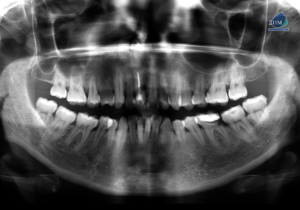

Caso 300 – IDM – HIPERPLASIA DE APÓFISIS CORONOIDES DE LADO DERECHO – IDM

Paciente femenino de 16 años acude al Instituto de Diagnóstico Maxilofacial (sede Miraflores) para evaluación quirúrgica. Radiografia Panorámica A la evaluación de la radiografía panorámica